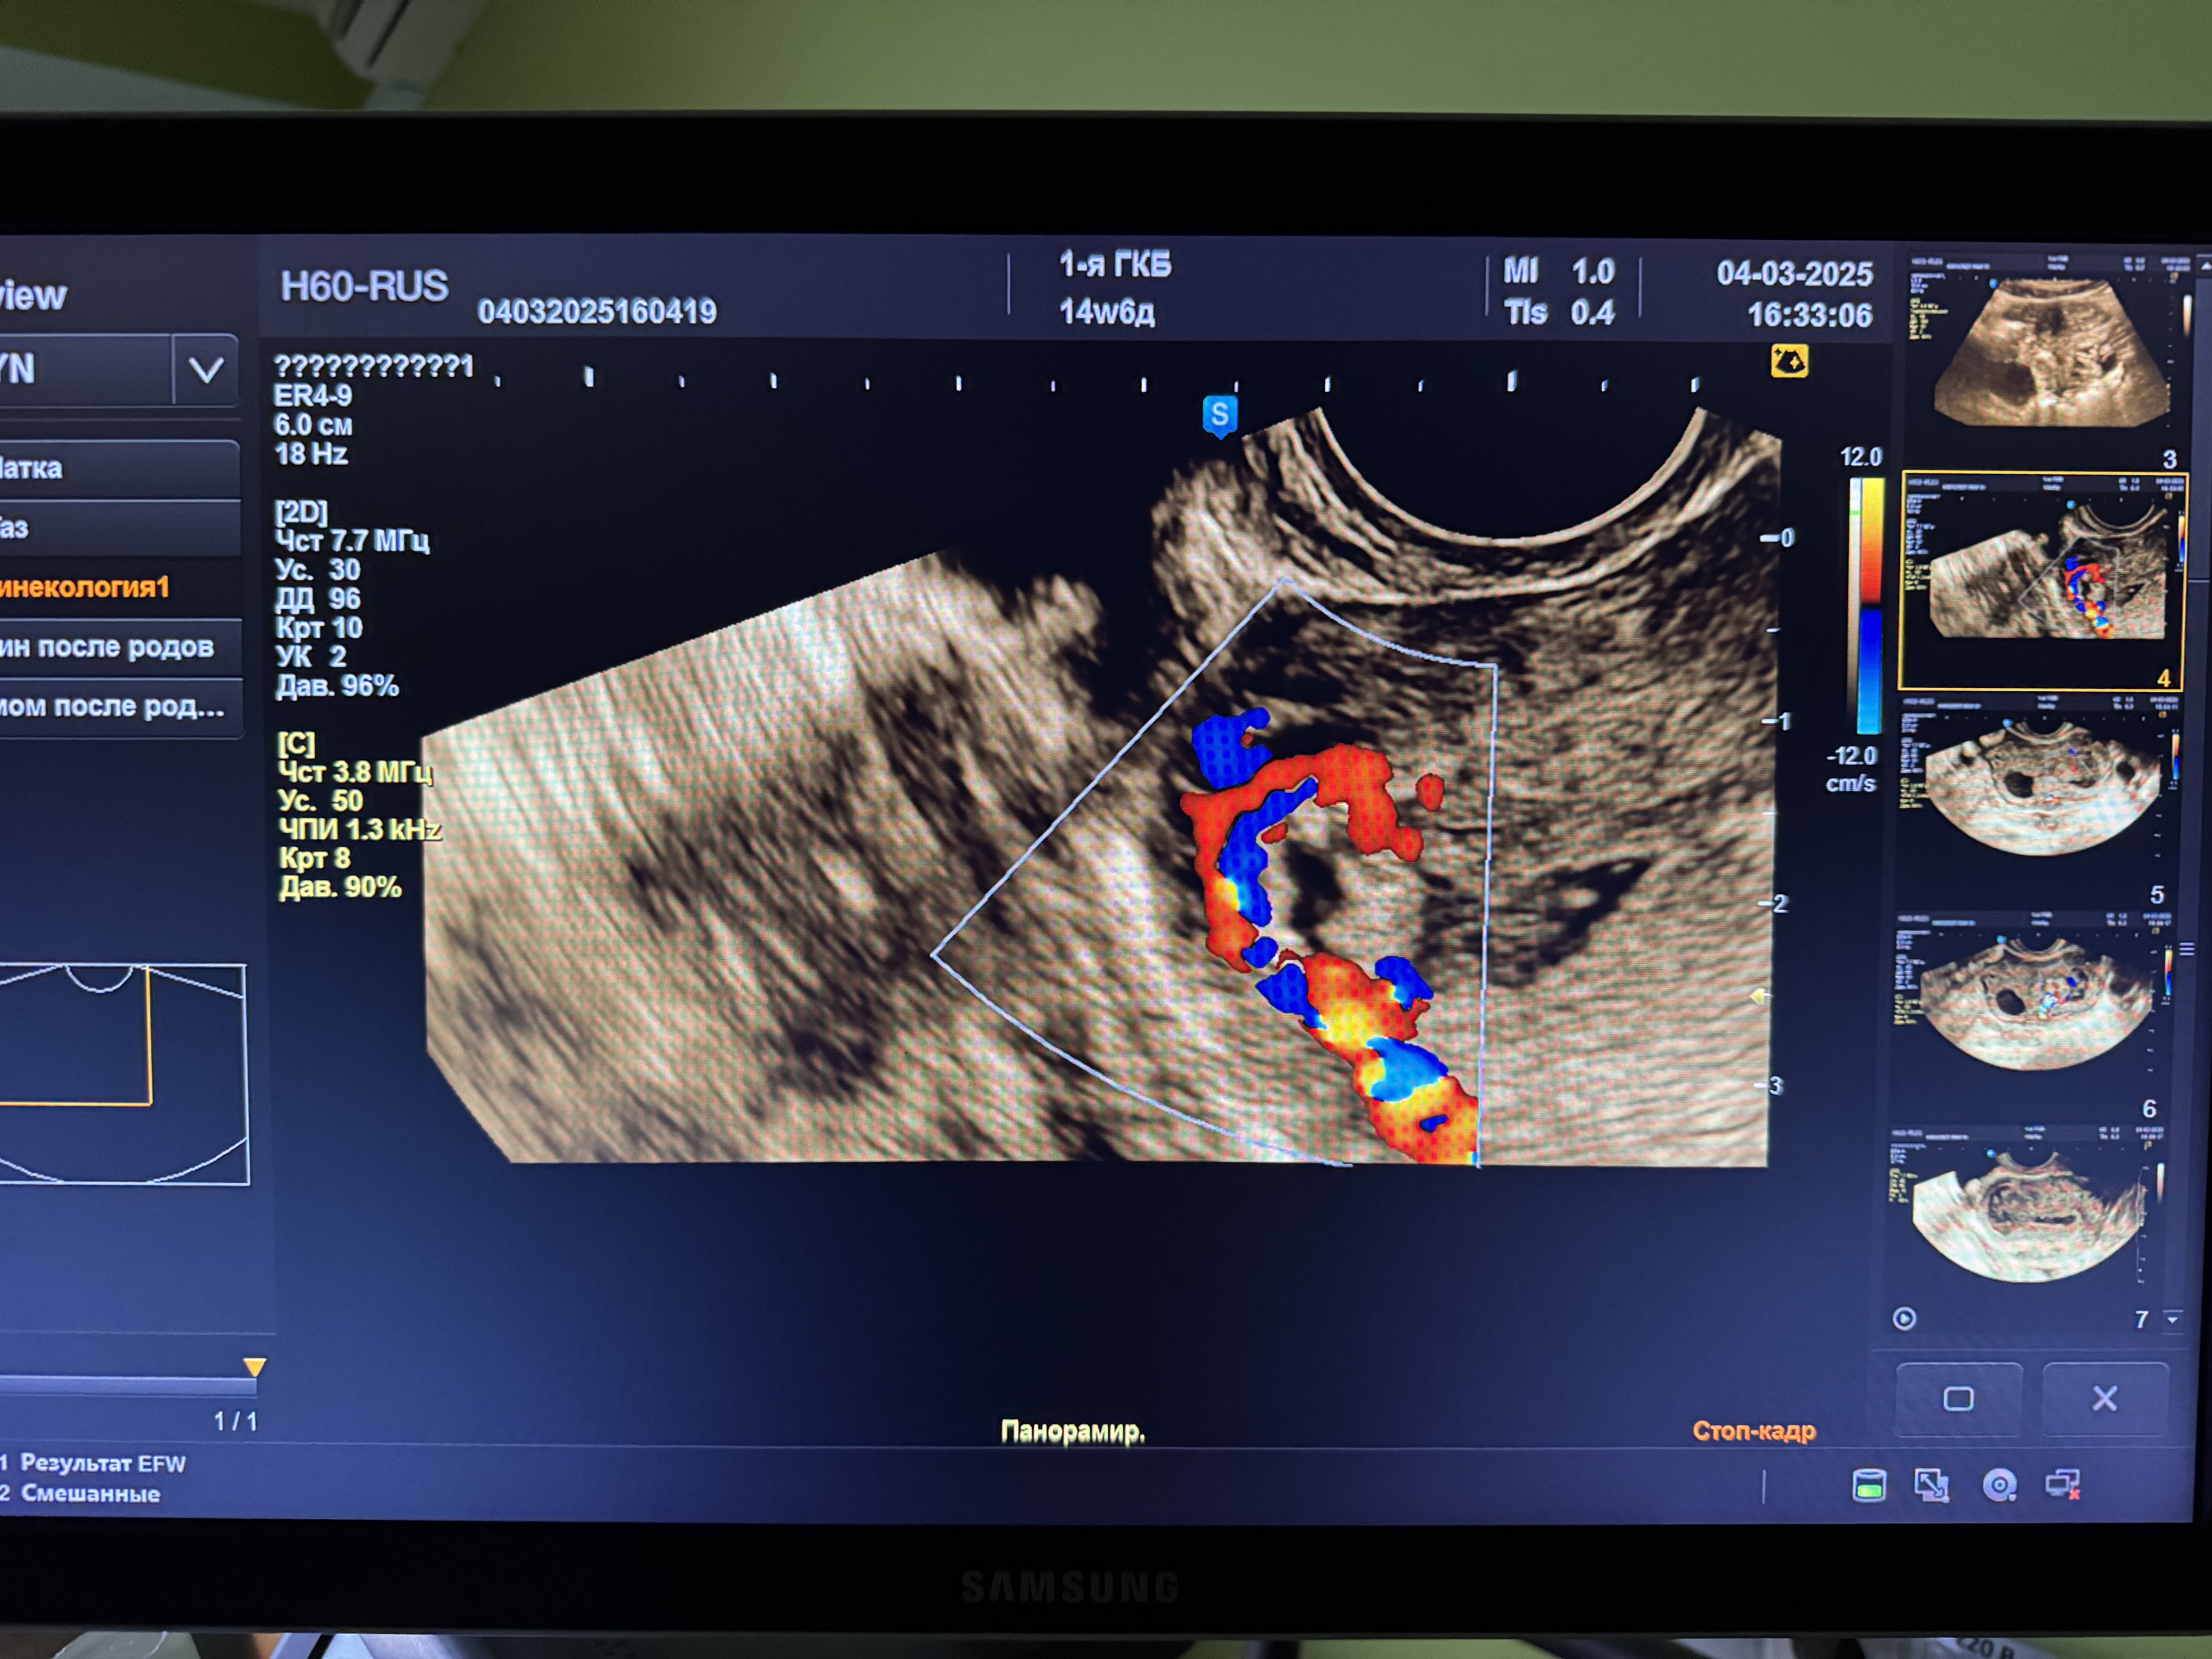

сделала 2.03 узи, нашли гематометру, остатки плодного яйца.

направили в стационар на чистку, сегодня сделали узи и подозревают новую беременность малого срока,а может и это от старой остатки, точно ответить мне не могут, хгч я сдавала от 27.02, 4254

Марина, добрый вечер, плодное яйцо вроде как и видят и хорион, врачи не могут ни подтвердить ни опровергнуть новую беременность,т.к если это она , то только все формируется, в любом случае, что-то со мной происходит, новая б на фоне старой, неполный пузырный занос или просто остатки старой беременности, конкретики нет, завтра назначена гистероскопия, пообщаюсь с врачом .. обновлю свой дневник, 99%, что будут делать выскабливание , а там ждать гистологию